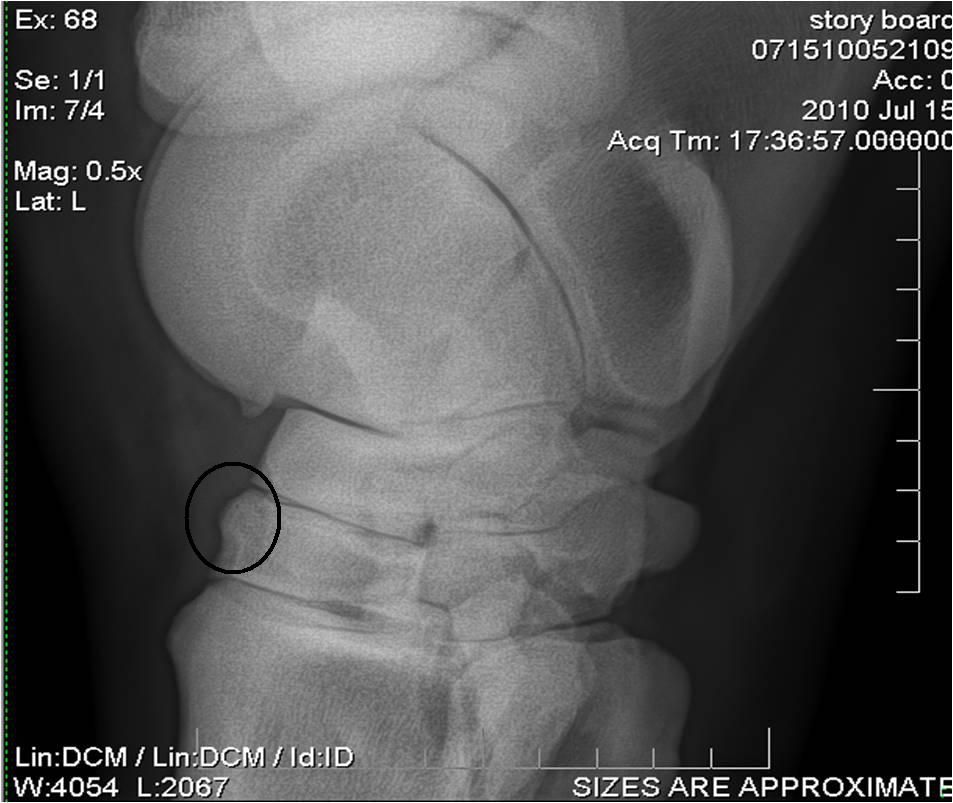

Déconnecté | Je viens enfin de récupérer les 3ième radios de mon cheval qui souffre d'un éparvin Le véto m'a montré ou c'était (j'ai fais des ronds pour vous montrer) mais apparement, il n'y aurait pas que ce que je montre dans le cercle, l'éparvin se voit aussi à un autre endroit. Quelqu'un sait me le dire ? Première radio à 4 ans [url=https://www.1cheval.com/membre/services/photos/images/137389.jpg] ![]() [/url] deuxième radio en avril 2012 [url=https://www.1cheval.com/membre/services/photos/images/137390.jpg] ![]() [/url] Et troisième radio fin septembre qui montre une évolution postive (éparvin en cours de solidification après avoir reçu du Tildren en juin) [url=https://www.1cheval.com/membre/services/photos/images/145646.jpg] ![]() [/url] Je crois qu'il y a une histoire de tassement des étages osseux ? On le voit bien sur la troisième radio... Bref aux profs des radios pouvant m'éclairer encore et encore ! Merci |